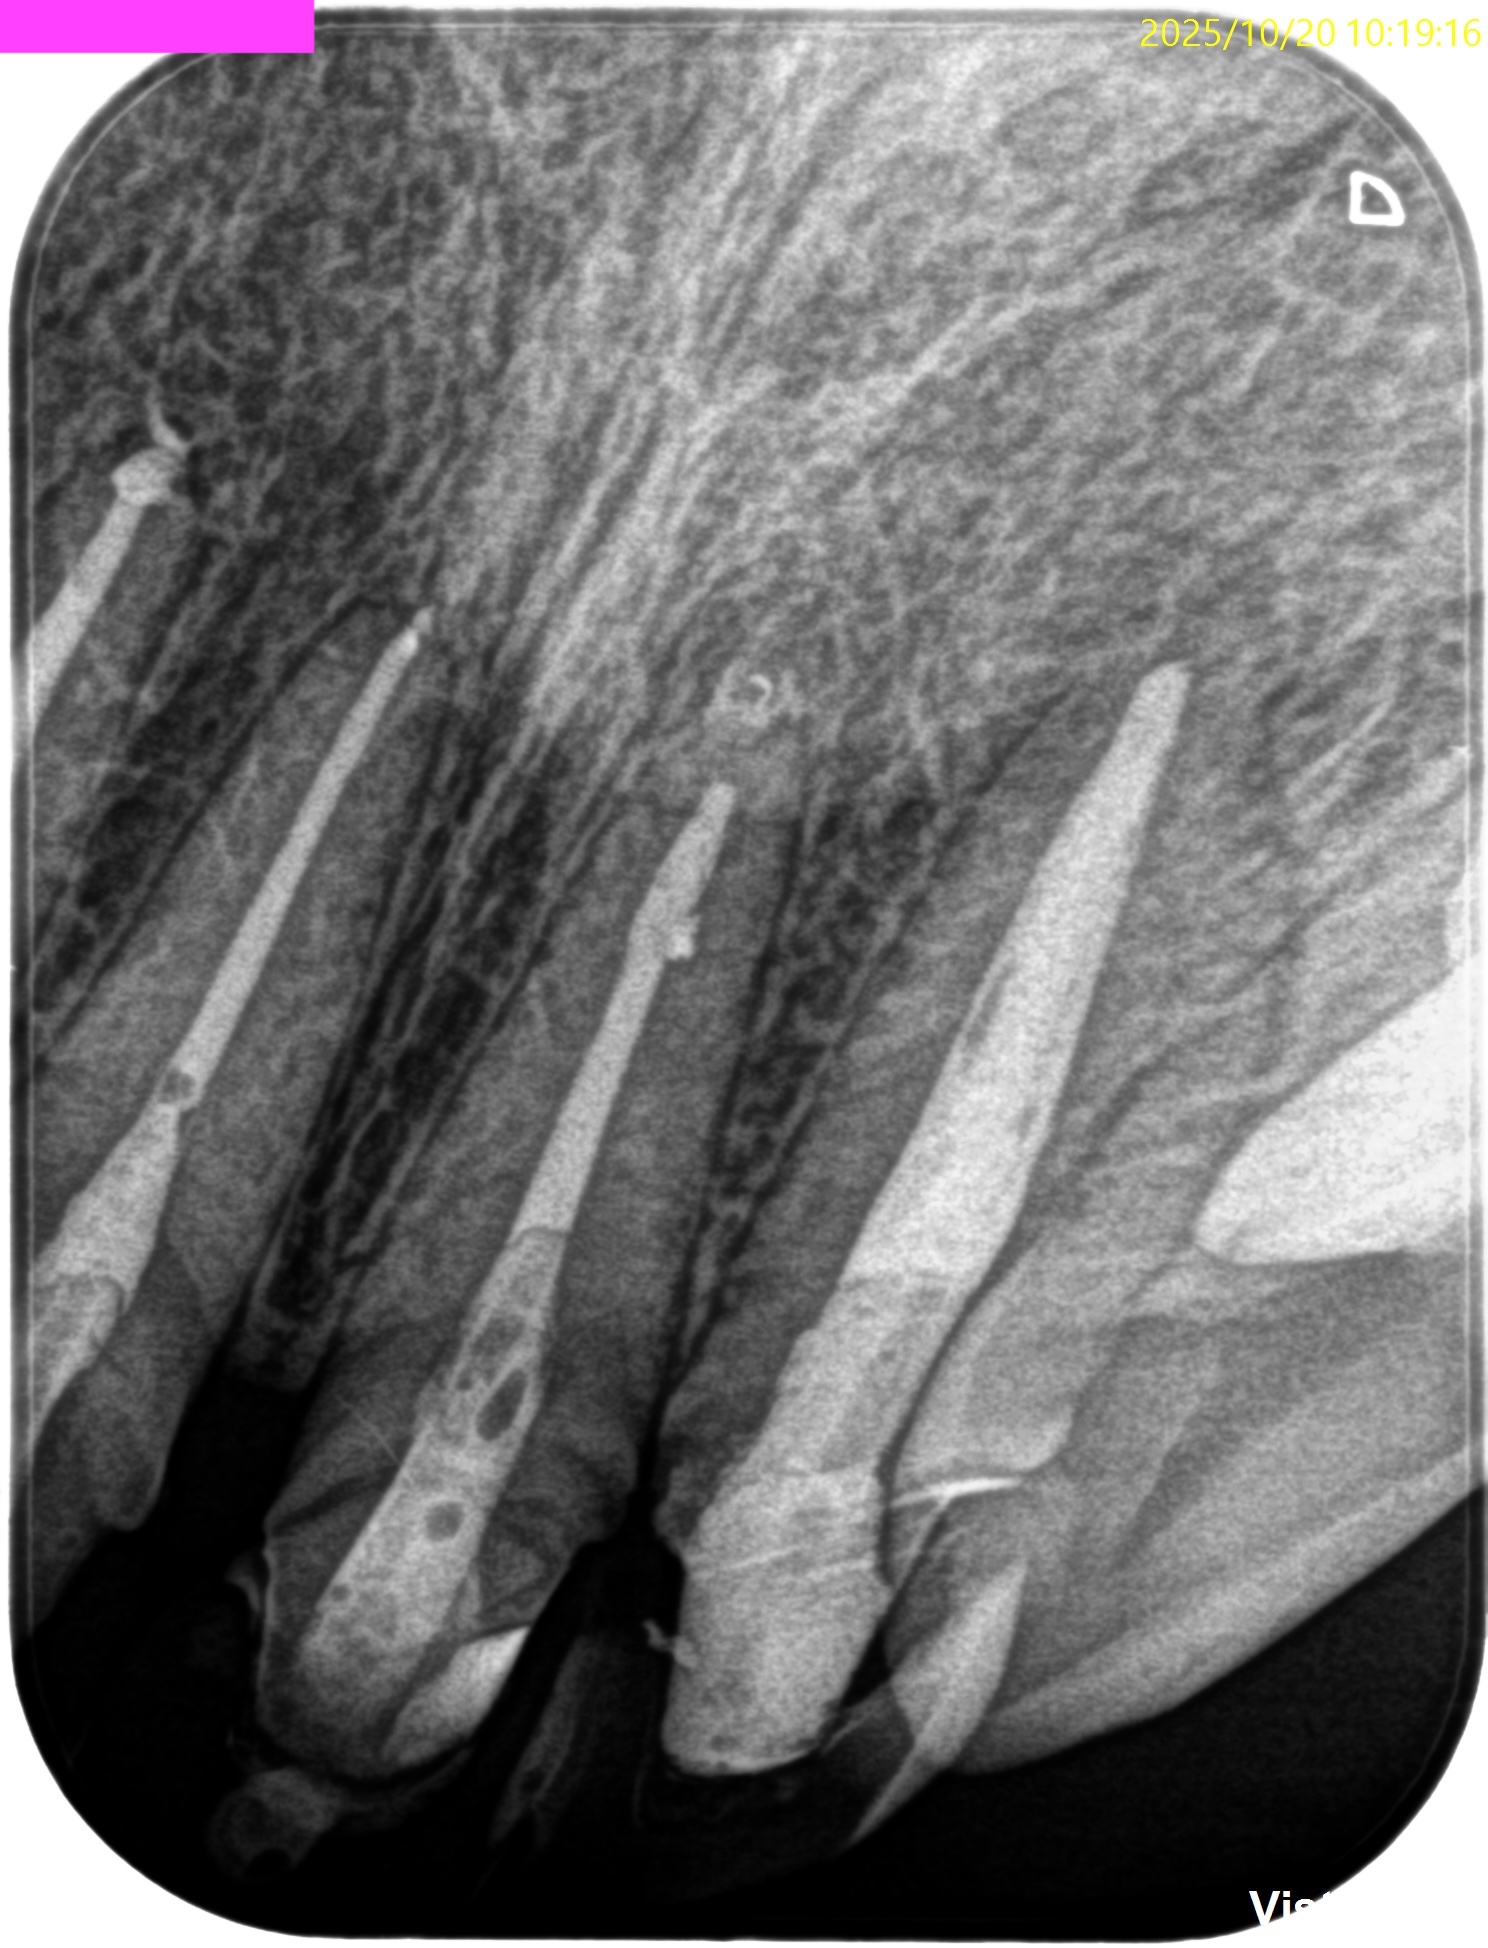

#7,10 Re-RCT 10M recall(2025.10.20)

症状が消失している。

ということは、治癒しているのだろうか?

が、この絵だけで治癒しているかどうか?判断がつくだろうか?

無理だ。。。

そこで、CBCTも撮影した。

#7

#10

これでも判然としかねる。

そこで、

CareStream(日本ではヨシダ社)のCBCTなら以下のようにMPR(Multi-Planar Reconstruction)画面を作成することができる。

それを過去のそれと比較してみた。

↓

このMPR画像からこの患者さんは#7,10ともに外科治療など要らないということがわかるだろう。

無論、検査の結果からそれは必要はないと言えるが、

客観的に不要であるということを患者さんに伝えるにもこの画像機能(MPR画像)は非常に有効である。

ということで今日は、このMPR画像機能について論じてみた。